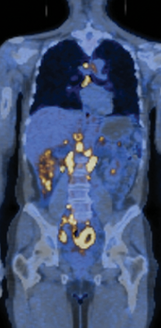

只有当肿瘤是恶性的(malignant),即其细胞获得了侵袭周围组织的能力时,才被视为真正的癌症。侵袭性是癌细胞的一个基本特征。这使得它们能够脱离原发部位,进入血液或淋巴管,并在身体其他部位形成被称为转移灶(metastases)的继发性肿瘤(图20-1)。通常,癌症扩散得越广泛,就越难以根除。正是这些转移灶通过导致重要器官功能衰竭,通常成为癌症患者死亡的原因。

图 20-1 转移。恶性肿瘤通常会导致转移,使癌症难以根除。这张融合图像显示的是一位转移性非霍奇金淋巴瘤 (NHL) 患者的全身扫描图。背景图像由 CT(计算机 X 射线断层扫描)扫描获得。叠加在此图像上的 PET(正电子发射断层扫描)扫描显示了肿瘤组织(黄色),该组织通过其对放射性标记的氟脱氧葡萄糖 (FDG) 的异常高摄取率被发现。高 FDG 摄取率发生在葡萄糖摄取和代谢异常活跃的细胞中,这是癌细胞的特征(见图 20-18)。腹部的黄色斑点揭示了多处转移灶。

肿瘤细胞即使在氧气充足的情况下也倾向于弱化氧化磷酸化,同时大量摄取葡萄糖,这种特性对许多癌细胞的快速增殖至关重要,被称为瓦博格效应——因奥托·瓦博格在二十世纪初首次发现此现象而得名。正是这种异常高的葡萄糖摄取能力,使得肿瘤能够在全身扫描中被选择性成像(见图20-1),从而为监测癌症进展及治疗反应提供了一种方法。